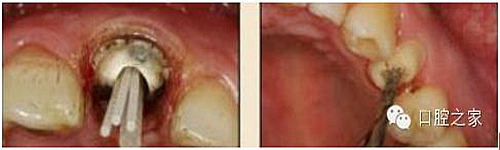

13.不規(guī)則根管的纖維樁粘接

普通纖維樁對圓形截面的根管適合性較好,而對不規(guī)則的橢圓形、喇叭形及 8字形等根管的適合性較差,臨床很難取得較好的粘接和修復(fù)效果。輔樁的應(yīng)用可改善圓形纖維樁對不規(guī)則根管的適合性(圖 24),增加了根管內(nèi)外樁核的整體強度,彌補了樹脂水門汀及核材料的聚合收縮,減少了微滲漏的發(fā)生,可明顯提高纖維樁對不規(guī)則根管的粘接效果。使用ELLIPSON技術(shù),采用專用的超聲根管預(yù)備鉆對扁圓形根管進行直接預(yù)備,改善了樁與根管形態(tài)的吻合性,有效地保存了根管牙體組織,從而達到了增加粘接面積,減少樹脂水門汀厚度,提高了根管內(nèi)纖維樁的粘接強度(圖25-1至圖25-3)?! ?/p>

圖24:輔樁的應(yīng)用。

圖25-1:紙ELLIPSON技術(shù)。

圖25-2:超聲預(yù)備根管完成。

圖25-3:插入橢圓形纖維樁。